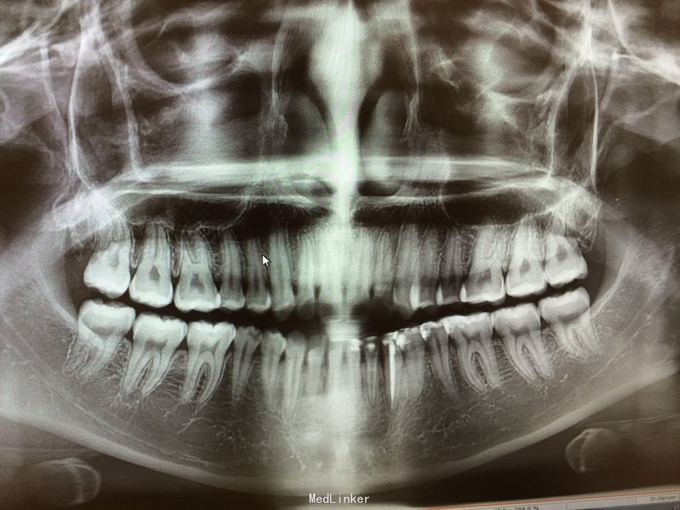

D3完全脱位,伤口血凝块已经凝固,颊侧牙龈钝性撕裂。D2D4无叩痛和松动。脱落牙齿牙体硬组织完好,牙周膜干裂,牙体上有纸屑和食物残渣,根尖有牙髓组织呈黑红色。

D3牙脱位 D3体外根管治疗后垫底充填,盐水和双氧水浸泡后,刮尽牙根的牙周膜后放置盐水和庆大霉素液中15分钟。局麻下刮除牙槽窝内血凝块至流鲜血后盐水和庆大霉素交替冲洗,明胶海绵拭干牙槽窝,浸泡好的牙体植入牙槽窝内并复位,舌侧树脂牙周夹板固定D123456,牙周上派丽奥。随诊

1天后复诊,3天后复诊,7天后复诊,一个月后复诊,3个月后复诊。1个半月后复诊未发现牙周有较大吸收和炎症感染。